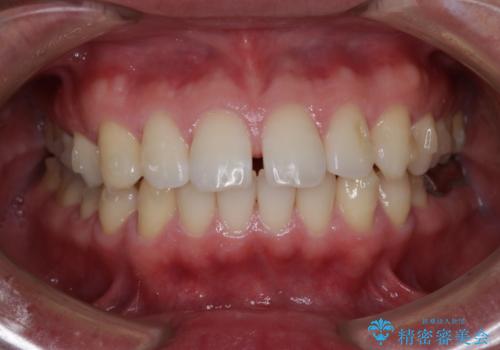

- 全体的に歯と歯の間に隙間があるのが気になるとのことで来院されました。インビザラインでの矯正治療をご希望されました。

隙間については、前歯と奥歯に多数あります。また、上下前歯は、外側に少し倒れているため隙間を閉じつつ、前歯を内側に引っ込めて並べることになりました。